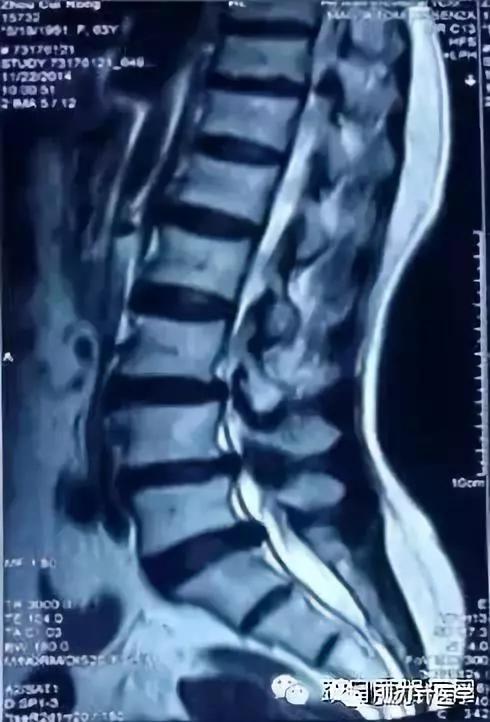

CT:诊断符合率96% —100%,正常CT椎管形态为三角形或球形,狭窄的可显示为三叶草、牛角、猫耳形。Korkard测量侧窝神经根管矢径大于5mm 为正常,4 mm 为临界.小于 3mm 为狭窄。椎管与椎体矢状径比值在椎弓板上切迹层面小于0.45 ,在椎间盘层面小于0.35可以确诊,硬膜囊与椎管矢状径比值如低于0.6 以下可以确认。近年来又有CT计算机图形计算椎管横截面积CSAC自L1-S1,逐渐加大,硬膜囊横截面积(CSADS)自L1-S1,逐渐减小,来评估椎管狭窄。 MRI :它不能提供精确的定位与清晰的图像,诊断符合率占 82%一 91%,但在鉴别诊断方面可显示椎管。